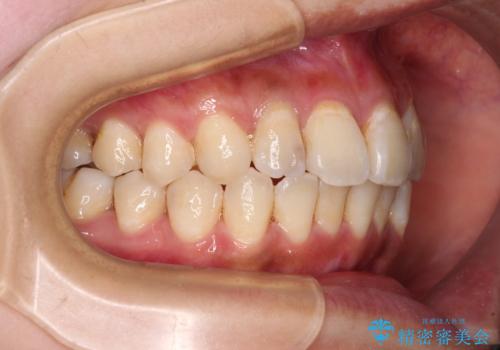

デコボコで磨きにくい前歯をスッキリと インビザライン矯正

- 虫歯が多く、磨きにくい歯並びを改善したいとのことで来院された患者様です。

歯列は叢生が認められる程度でしたが、やや前突感があったので、少しでも口が閉じやすくなるように仕上げる方針としました。

神経を取り除かれている歯3本以外にも虫歯が認められたため、事前に処置を行い、インビザラインにて矯正治療を行うこととしました。

歯磨きしやすくなるとともに、飛び出していた前歯も引っ込めて整えることができました。